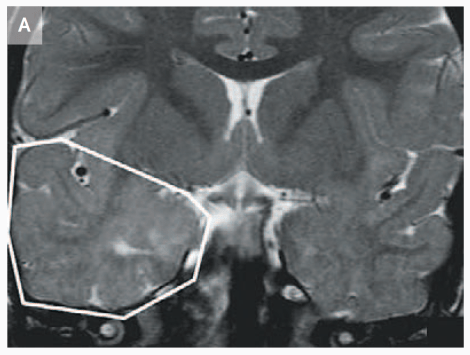

Evidence from mutations in the CNTNAP2 gene, which is part of the neurexin family, also suggest its importance in neuron development before and during neuronal migration. It’s been found that mice with a double knockout of the gene exhibit migrational abnormalities in the form of ectopias (misplaced cells), a finding that echoes human cases of Cortical Dysplasia-Focal Epilepsy (CDFE) syndrome that are linked withΒ CNTNAP2 mutation [4, 5].

MRI that shows increased volume in the temporal lobe of a 3 year-old child with CDFE syndrome (Strauss et al., 2006).